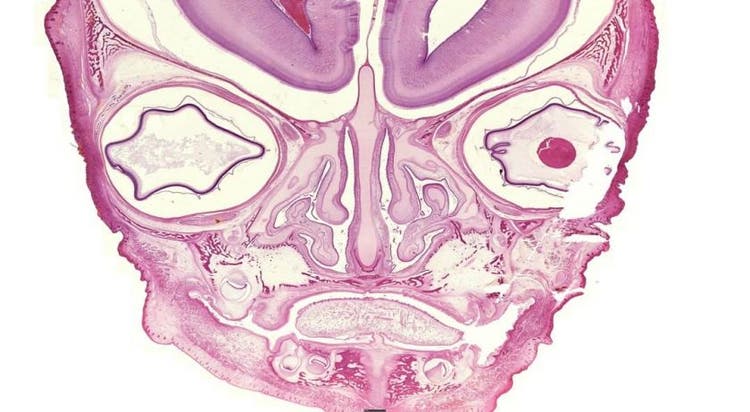

While this may look like a face with two eyes, a nose, and a mouth, this image is actually developing bone captured under the microscope!